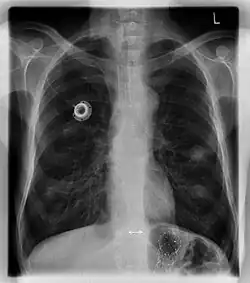

Рентгеновский снимок имплантированного порта.